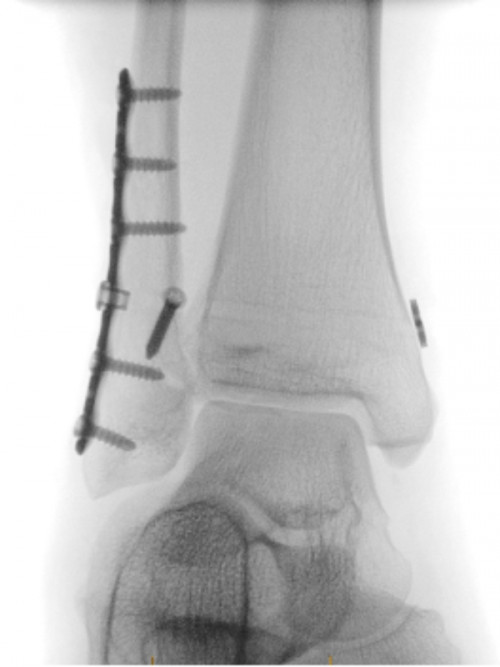

Orthopaedic surgery – fluoroscopy might be used by your surgeon to help guide procedures such as joint replacement or fixing broken bones.

Orthopaedic procedure also using fluoroscopy

Image credit: Allevia Radiology